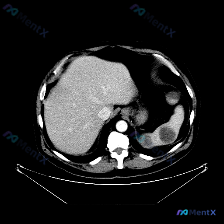

今天整理了一份上腹部增强CT的影像资料,结合临床分析思路,觉得挺有讨论价值的,分享给大家。 影像核心发现 上腹部增强扫描(软组织窗): - 肝脏:轮廓光滑,密度均匀,未见明确局灶性病变; - 脾脏:体积增大,实质内见多发圆形/类圆形低密度灶,边界相对清晰,增强后无强化或强化程度远低于正常脾实质; -...

今天看到一个挺有意思的影像分析场景:拿到一张上腹部CT横断面(软组织窗),问题直接指向“脾脏病变”,但仔细看完影像描述,我觉得这里可能藏着一个临床思维的小陷阱。先把资料理一理: --- 影像描述核心信息整理 肝脏:轮廓清晰,形态正常,肝实质密度均匀,未见明确局灶性占位,肝内血管走行自然。 脾脏:左上...

整理了一个很有意思的读片资料,先看一下基本情况: 影像资料概况 - 扫描部位:上腹部横断面CT(软组织窗) - 图像质量:清晰,对比度适中,无明显运动伪影 - 显示结构:肝脏、胃、脾脏、腹主动脉、椎体及周围软组织 主要影像描述(按器官整理) - 肝脏:形态轮廓尚平滑,实质密度均匀,未见明显局限性肿块...